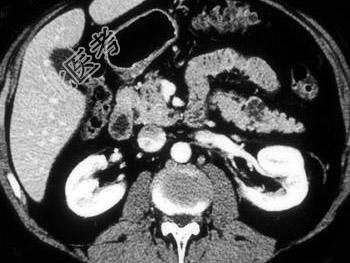

- 单项选择题对于胰尾病灶,结合图像, 最可能的诊断是 ( )

A、腺癌

B、转移癌

C、假性囊肿

D、胰腺粘液性囊腺瘤

E、脂肪瘤